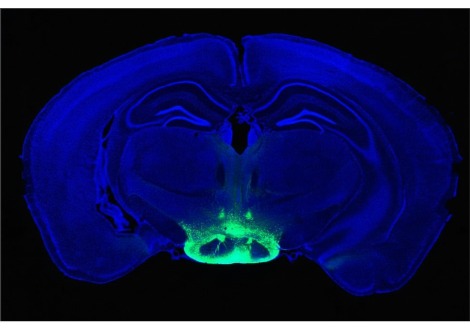

في الورقة ، وصفت مجموعة من الباحثين من هولندا زوجًا من الغدد اللعابية يطلق عليهما اسم "الغدد البوقية" لموقعها في الطارة البوقي ، وهو جزء في البلعوم الأنفي - الجزء العلوي من الحلق. استندت هذه النتائج إلى فحوصات الفريق لمئات من مرضى السرطان ، وتشريح جثتين بشريين ، وتصوير متطوع واحد سليم. بعد اكتشاف أن التعرض للعلاج الإشعاعي كان مرتبطًا بجفاف الفم وصعوبات البلع في مجموعة بيانات تم جمعها مسبقًا لأكثر من 700 مريض بسرطان الرأس والرقبة ، لاحظوا أن هذه الغدد قد تكون معرضة لخطر التلف من هذا العلاج.